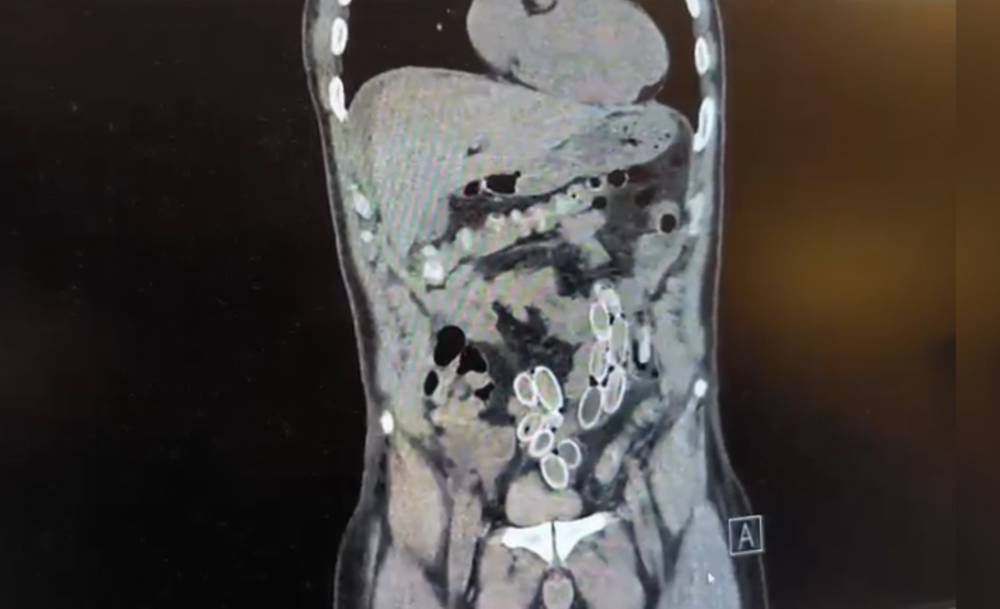

Tomografisi çekilen Cüneyt Ç.'nin mide ve bağırsaklarında yabancı madde bulunduğu tespit edildi. Hastane yetkililerinin bilgi vermesi üzerine Beşiktaş Asayiş Büro Amirliği ekipleri tarafından konuyla ilgili çalışma başlatıldı.

Fas'tan yaklaşık 3 bin kilometre uzaklıktan uçakla Türkiye'ye gelen Cüneyt G., 2 gün sonra karın ağrısı şikayetiyle Fulya'daki özel bir hastaneye başvurdu. Yapılan muayenenin ardından Cüneyt G.'nin tomografisi çekildi. Şüphelinin mide ve bağırsaklarında yabancı madde tespit edilmesi üzerine hastane yetkilileri durumu polis ekiplerine bildirdi.

İhbar üzerine çalışma başlatan Beşiktaş Asayiş Büro Amirliği ekipleri, doktorlarla görüşme gerçekleştirdi. Doktorların değerlendirmesi sonrası ameliyata alınan Cüneyt Ç.'nin bağırsaklarından, toplam ağırlığı 259,7 gram olduğu öğrenilen 49 esrar macunu çıkarıldı. Şüpheliye ait 1 adet cep telefonu da hastane yetkilileri tarafından polis ekiplerine teslim edildi.